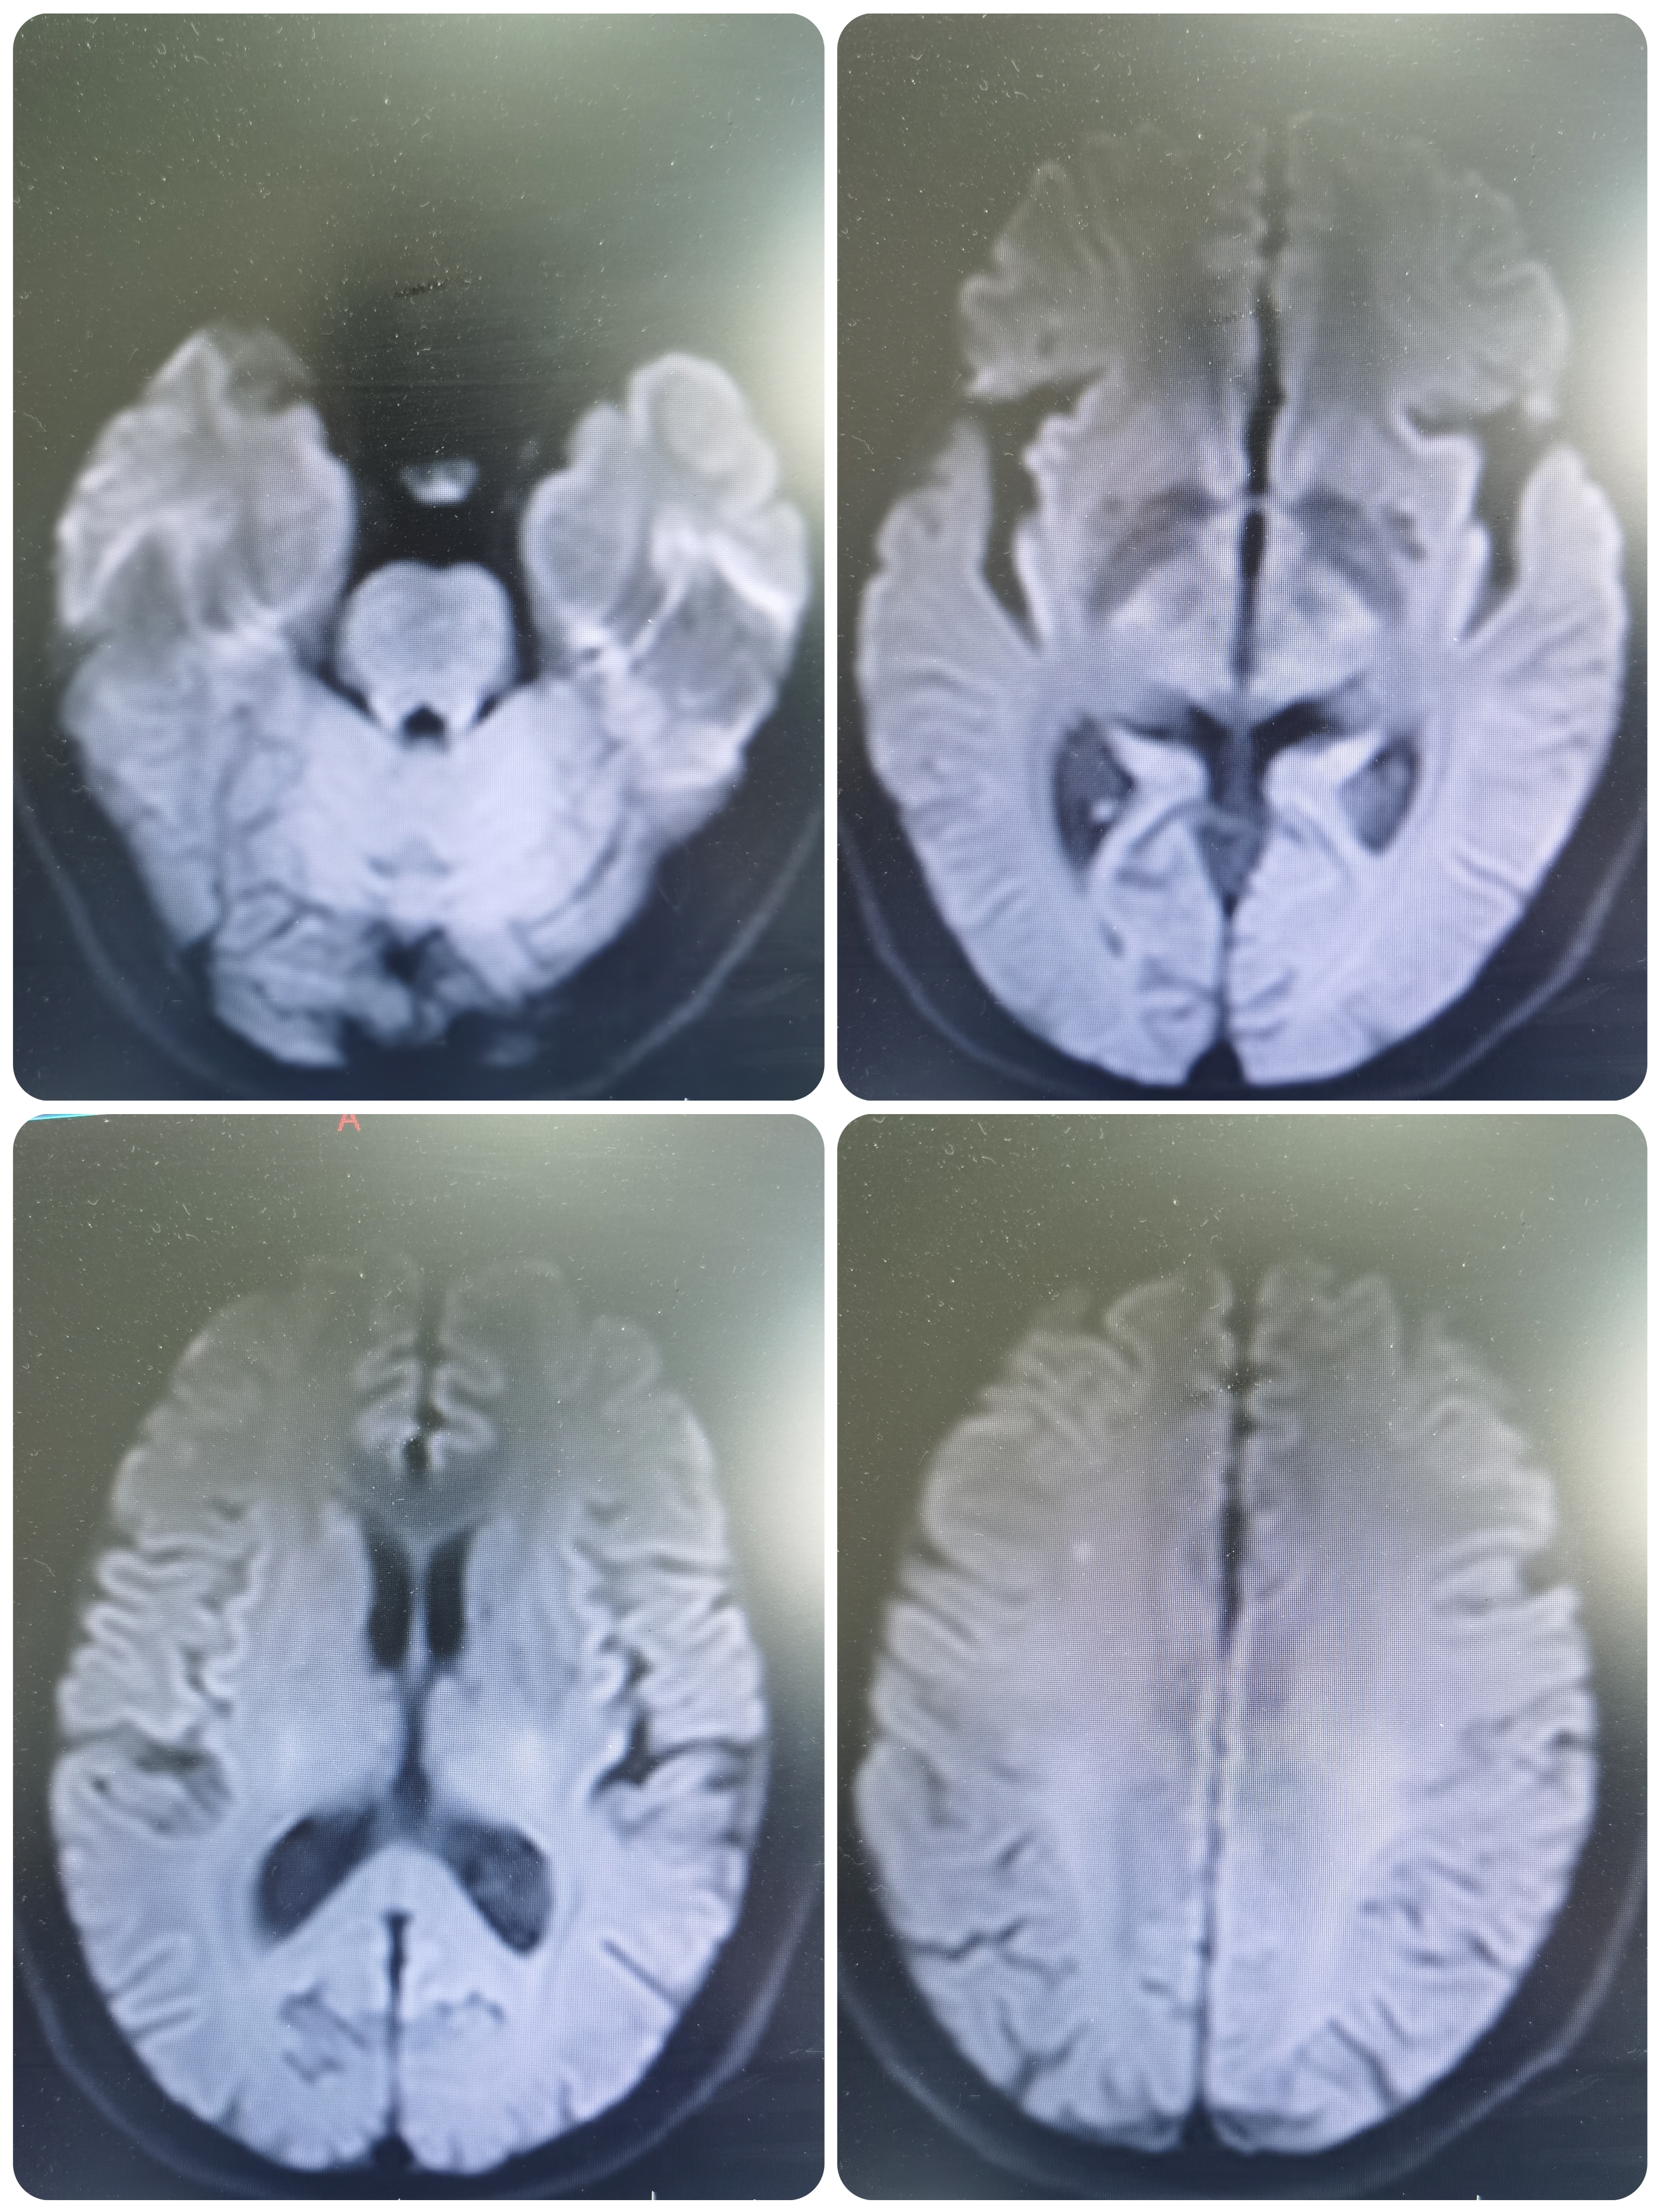

院前核磁提示右侧半卵圆中心新发脑梗死。

MRA示右侧大脑中动脉重度狭窄。

患者新发梗死入院,病灶位于右侧半卵圆中心,血管提示右侧大脑中动脉重度狭窄,系责任血管,患者存在高危因素,应积极治疗。在强化药物治疗后症状稳定,为进一步评估颅内血管情况,建议完善脑血管造影,必要时介入治疗。

术前术后对比

1、本例患者右侧大脑中动脉重度狭窄,远端低灌注梗死,有卒中危险因素,日后再发恶性卒中风险较大,应积极处理。